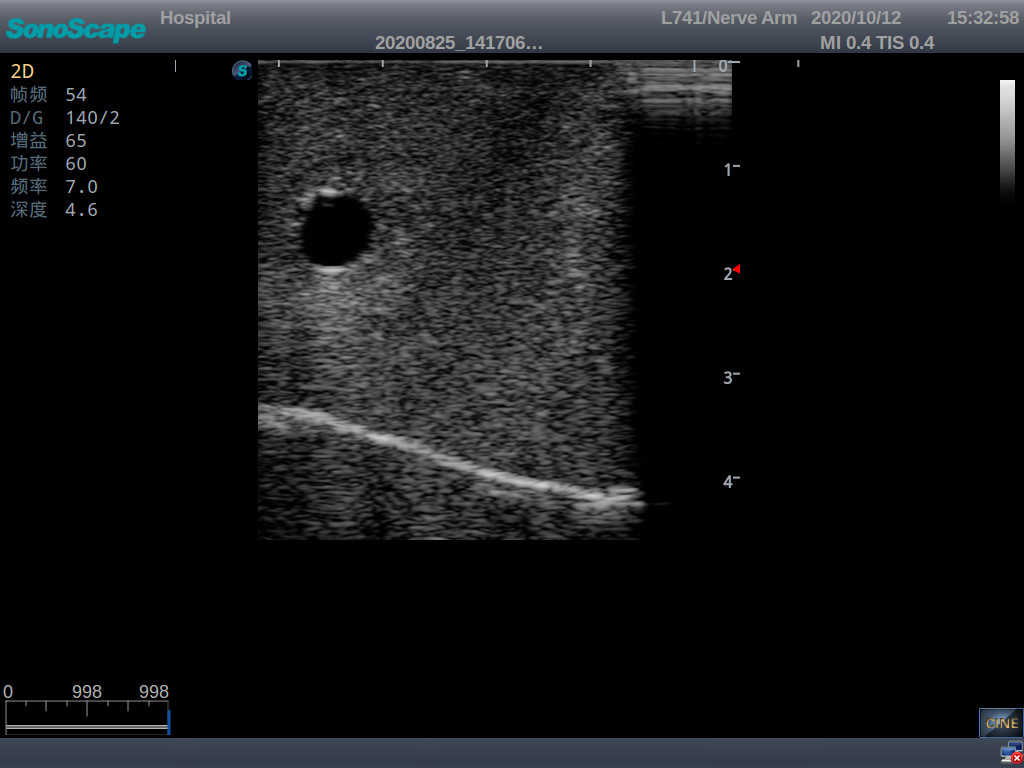

Central Venous Catheterization Ultrasound Training Model

Model TYE1510.2

It is a model from the earlobe plane to the umbilical plane with its head turned to one side. It's put in a standard central venipucture and catheterization position, including landmarks such as right arm, clavicle, ribs, sternocleidomastoid muscle, sternoclavicular joint, etc. It can be used for ultrasound-guided subclavian vein and internal jugular vein puncture and catheterization. The model's arm can be used for ultrasound-guided PICC catheter placement.

2)  The puncture module supports using a clinical real ultrasound machine to observe clear images such as right internal jugular vein, right common carotid artery, superior vena cava, right brachiocephalic vein, right brachiocephalic trunk, right subclavian vein, right subclavian artery, etc.

3)  The puncture pad at the arm is made of high-molecular ultrasound material, close to real skin. It can support the use of real ultrasound machines, and the images of tissue structures (skin, subcutaneous tissue, blood vessels) under ultrasound are clear and real

5)  The guide wire’s march can be observed under the guidance of ultrasound, and also whether the catheter is placed correctly can be detected